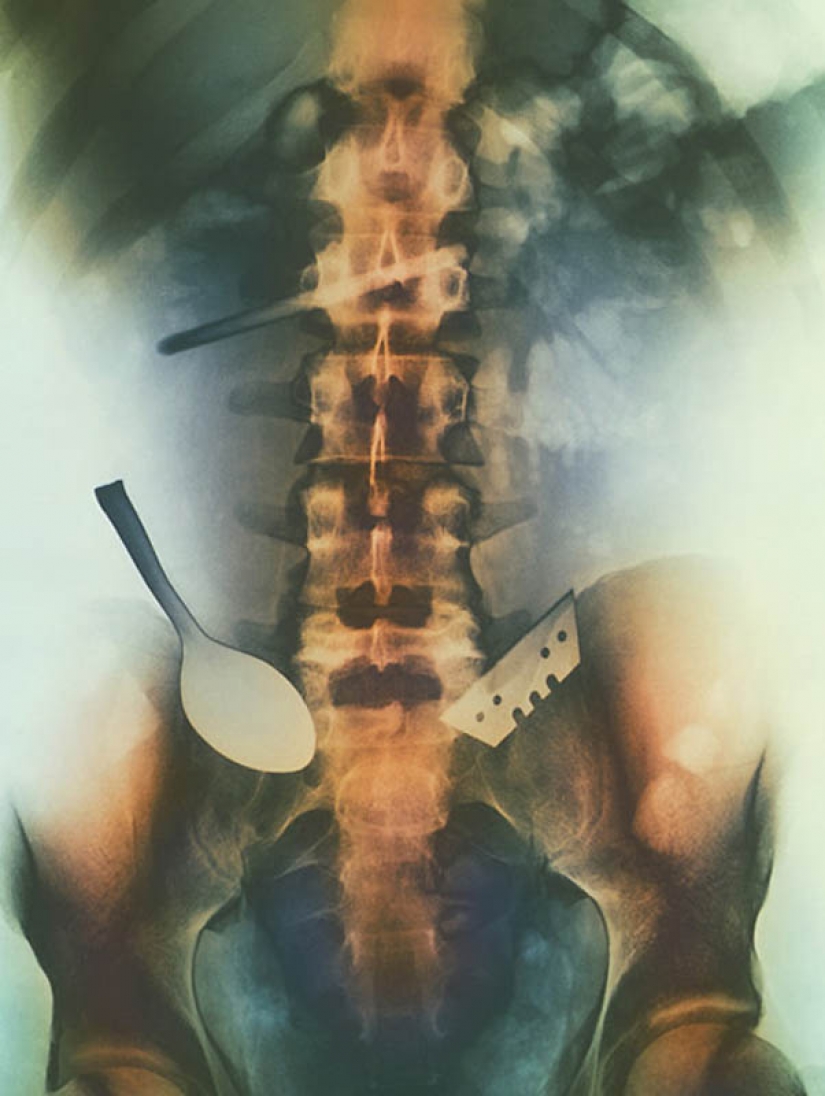

5. Color de los objetos que son ingeridos por el paciente, y se clavó en su estómago, incluyendo la cuchara y la cuchilla.